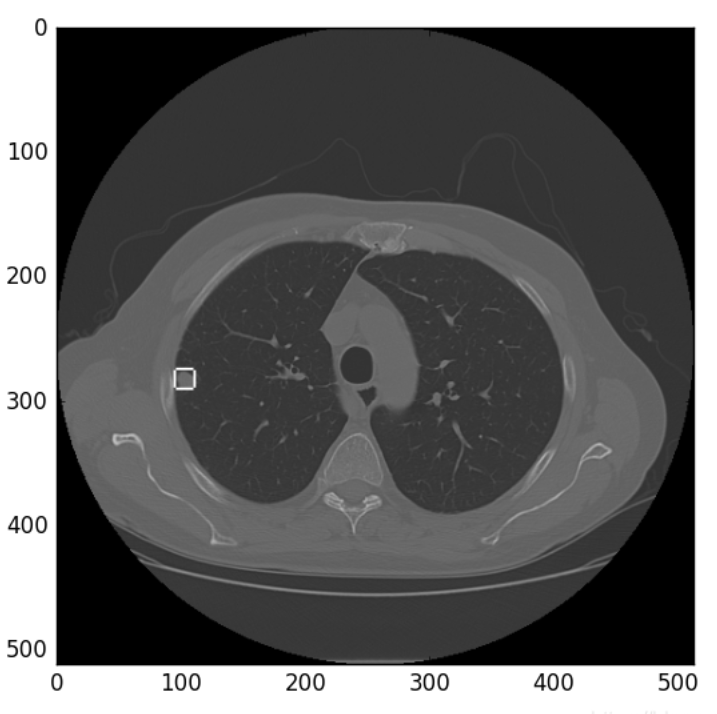

让我们一起可视化看下效果。

可视化之后的结果如下所示